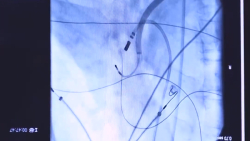

چکاپ آرتیمی قلبی